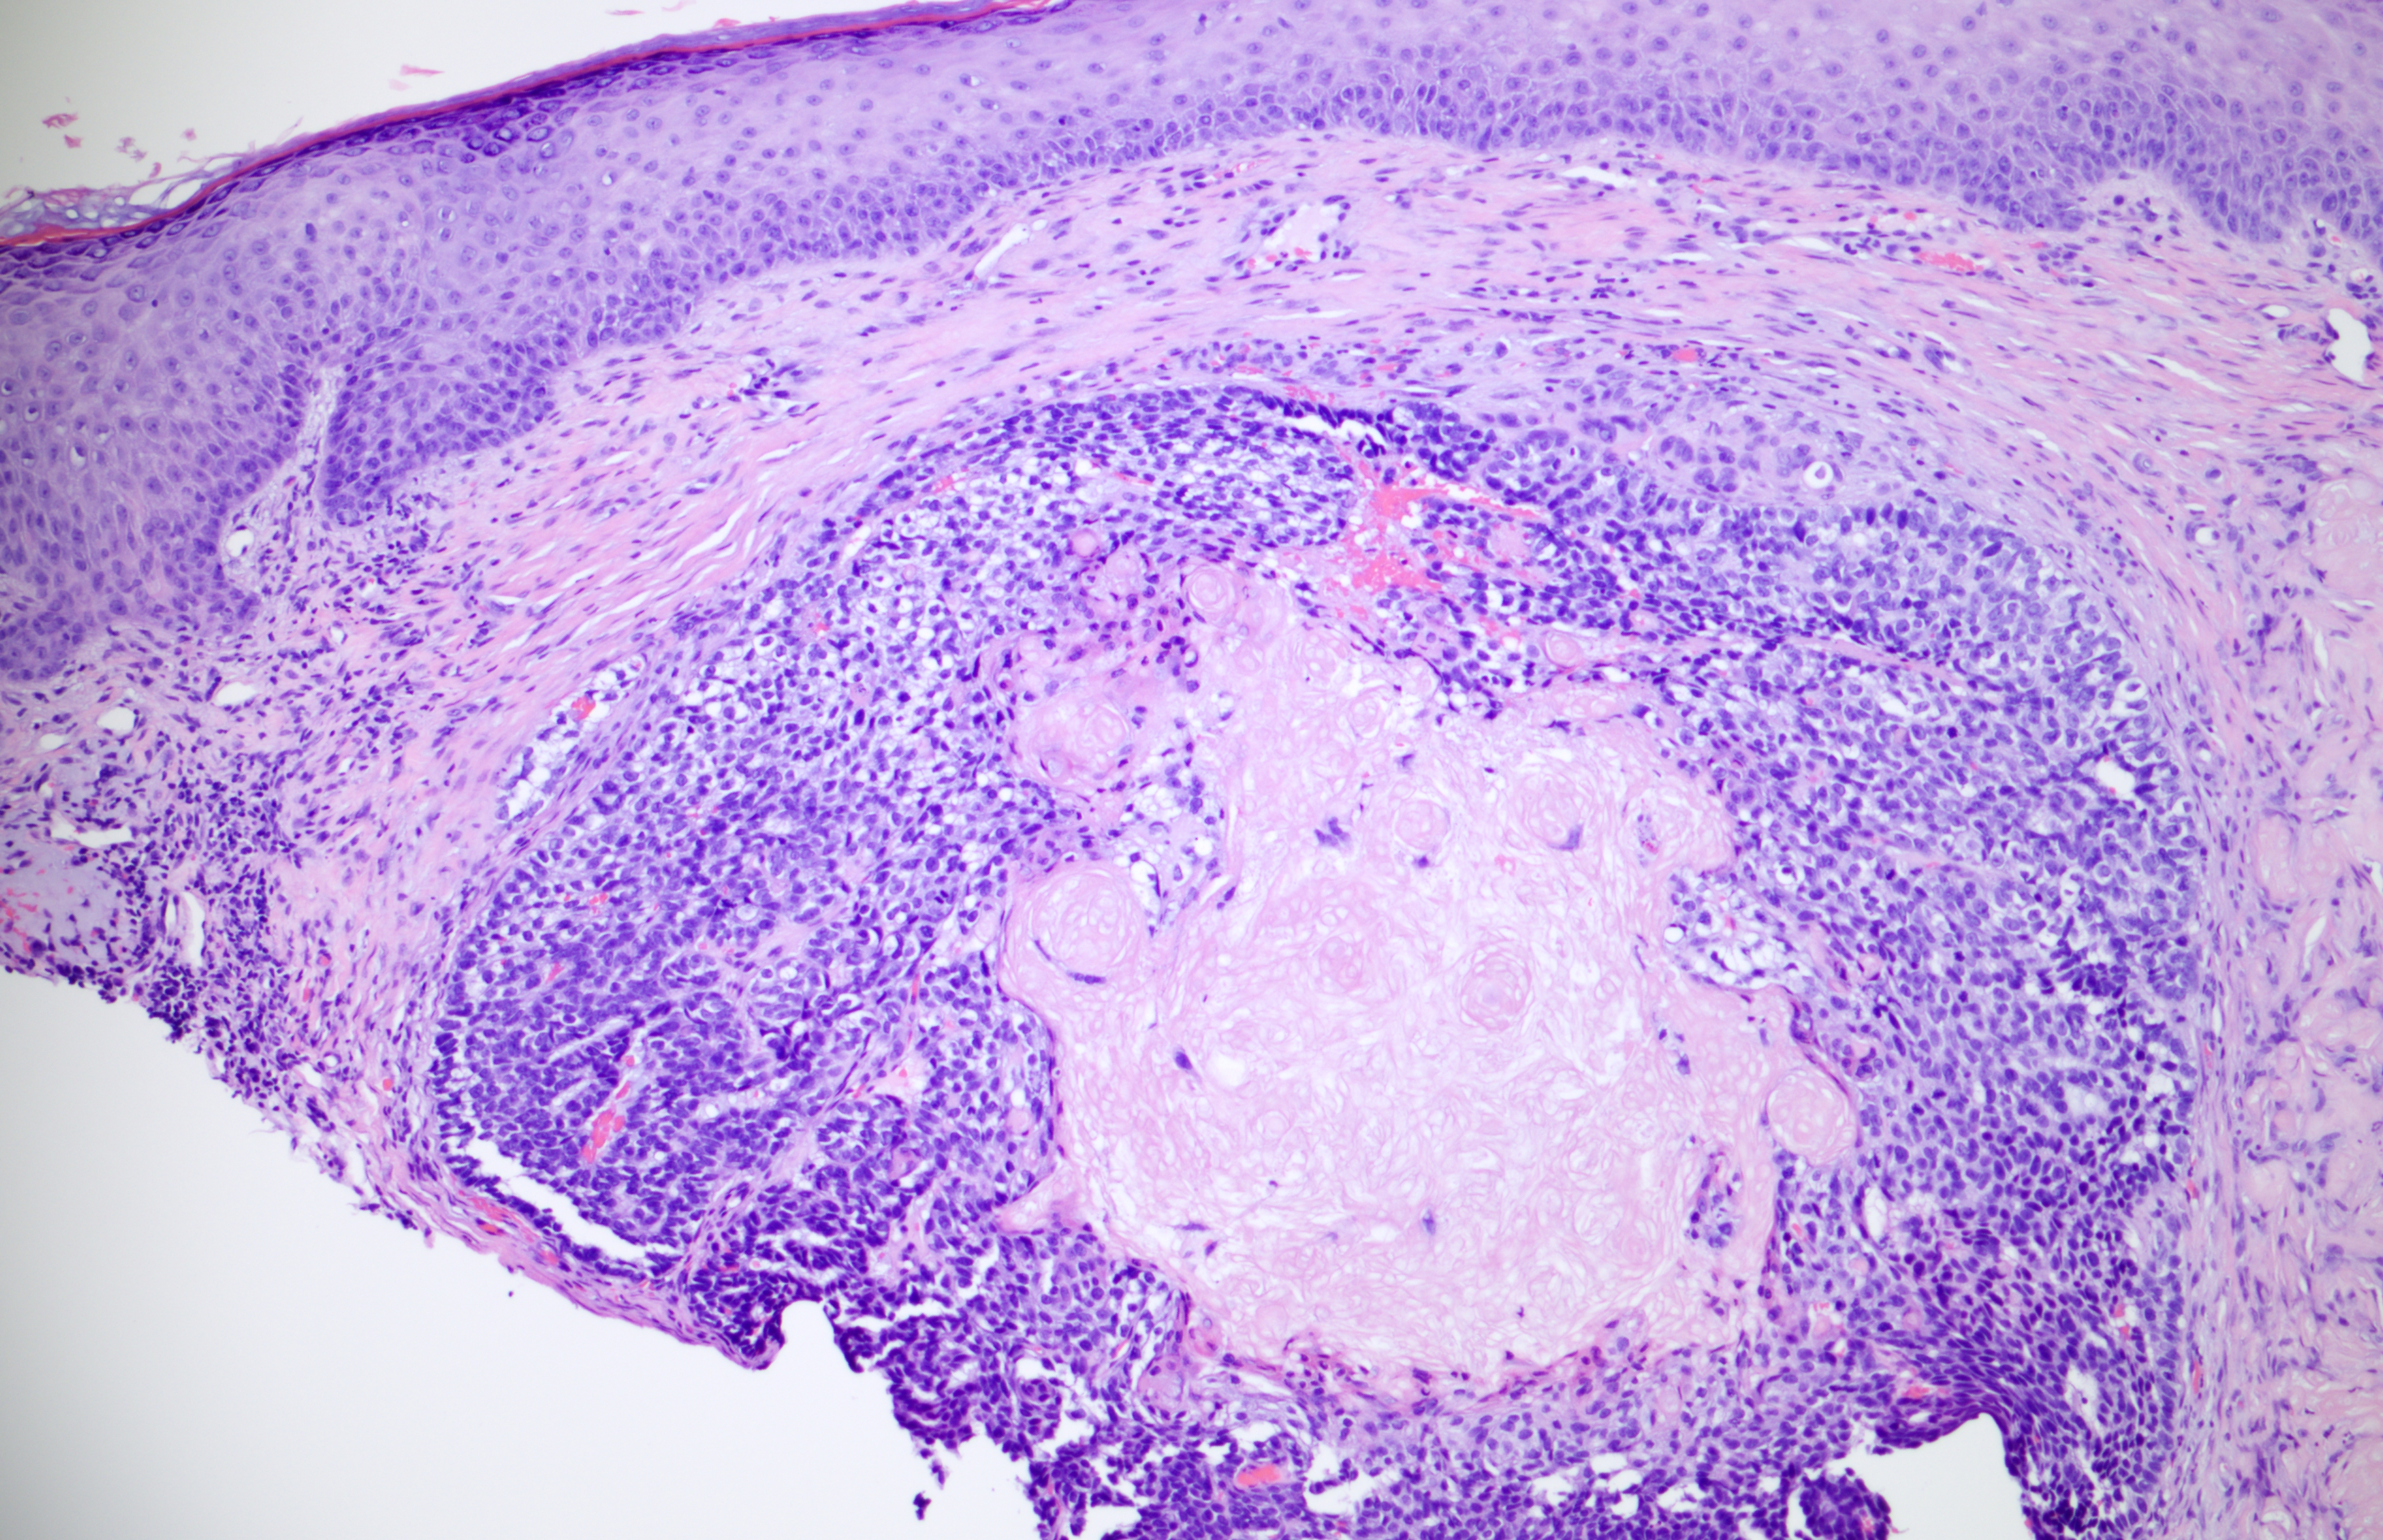

Papule on the nose of an 81-year-old male.

Agree with “question mark”, because of atypical features....?Malherbe ?Pilomatrical carcinoma

I cant easily sign out a pilomatrical carcinoma. Both benign and malignant counterparts of this entity tend to be mitotically active and usually have some atypical features. Maybe this is one of those cases which p53 is useful. WHO speaks for necrosis and irregular borders for malignancy. Could it be one of the cases that Kazakov uses the term atypical pilomatricoma (?)

The diagnosis is pilomatrical carcinoma.

Looks more like a BCC with matrical differentiation. Basaloid cells with peripheral palisading and pleomorphism do not fit into pilomatrix Ca. BER, CDX2, Beta cat, LEF1 if available

Thank you for your comments. The final diagnosis is: Pilomatrical carcinoma